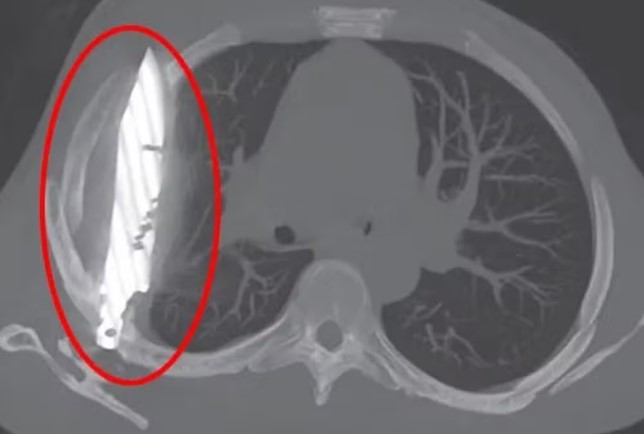

Já no hospital após oito anos, foram feitos exames radiológicos que revelaram uma lâmina alojada no lado direito do tórax, próxima à escápula, sem atingir órgãos vitais, mas no local havia secreção com pus, que foi atribuída à presença do corpo estranho e tecido danificado ao redor.